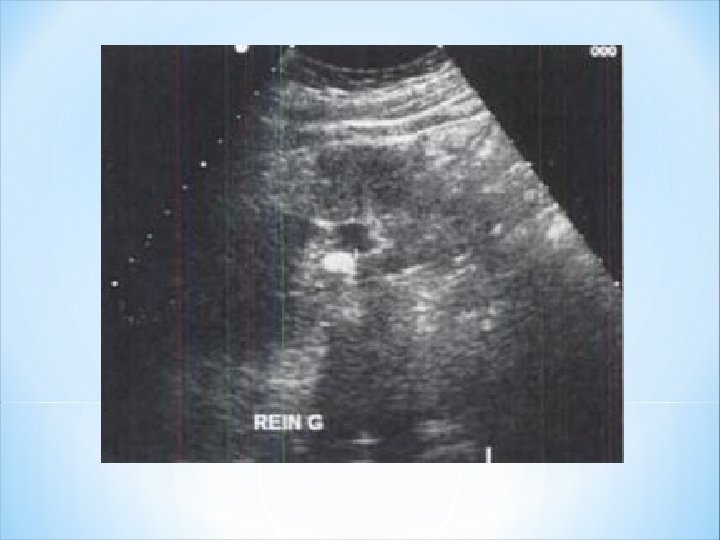

* Résultats: détecter les calculs mesurant 5 mm voire 3 mm Arc hyperéchogène + ombre acoustique Aspect identique quelle que soit la composition chimique du calcul. En pratique: le diagnostic de calcul est fiable en échographie ≥ 4 mm. * Diagnostic différentiel: interfaces acoustiques entre les différents constituants du sinus. calcifications athéromateuses des parois vasculaires. calcifications séquellaires du parenchyme au contact du sinus. air dans les cavité

1 - Échographie • Association d’un arc hyperéchogène avec son ombre acoustique. • Permet de détecter les calculs mesurant 4 mm voire 3 mm dans les conditions techniques optimales. L’aspect échographique est identique quelle que soit la composition chimique du calcul et son aspect radiologique. Limitée: pour évaluer la taille exacte et le nombre. • AUSP+ l’échographie : Dg 98 % des cas. • Une dilatation des cavités excrétrices permet de mieux distinguer un calcul baignant dans un milieu anéchogène des parois vasculaires